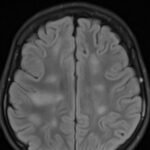

There is a growing body of literature and scientific discovery on pediatric autoimmune encephalitides. This is a heterogenous group of neuroinflammatory conditions leading to often perplexing acute and progressive neurologic and/or neuropsychiatric symptoms. This report demonstrates the evaluation and management of an adolescent with myelin-oligodendrocyte glycoprotein (MOG) antibody-associated fulminant acute disseminated encephalomyelitis (ADEM) in the context of current literature. The featured magnetic resonance imaging uniquely highlights progressive central nervous system lesions detected over the course of the first week of disease.